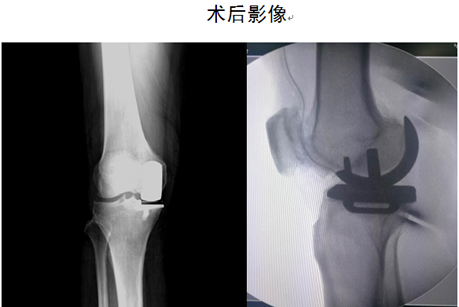

关节外科-创伤骨科主任马东印、副主任医师王兴龙通过详细查体及全面影像学检查,综合评估病情后,考虑患者为单纯右膝关节内侧间室骨性关节炎,外侧间室关节软骨尚完好,且十字韧带及内外侧副韧带也均完好。患者年龄刚六十有余,若行全膝关节表面置换为时尚早,更为可惜的是,手术需切除患者完好的外侧间室软骨及正常的十字韧带,虽能缓解疼痛,但关节功能会受很大影响,患者将不能进行深蹲、快走等灵活性活动。经过和患者充分沟通,决定为其行“右膝内侧单髁关节置换术”。经过仔细制定个体化手术及术后康复方案后,成功为患者实施了右膝关节单髁置换手术。术后第二天患者即下床活动,第五天即行走自如,彻底解决了患者疼痛及关节功能问题。

1.微创、手术切口小(10cm左右),相对于全膝关节置换手术,单髁置换手术可以说是关节置换手术中的微创手术;

2.切除骨质少,植入物小;